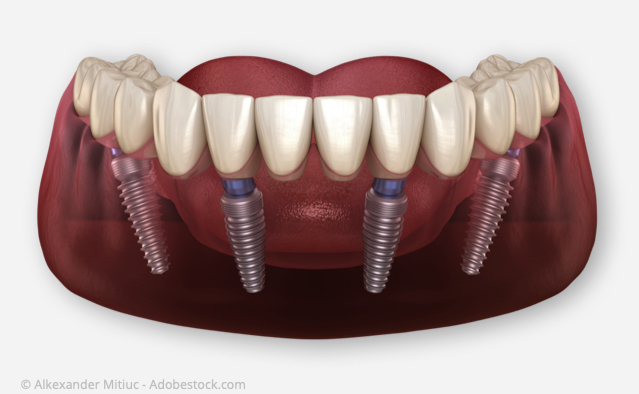

Wörtlich übersetzt bedeutet All-on-Four "Alle auf Vier".

Gemeint ist damit, dass eine ganze Zahnreihe auf nur vier Implantaten befestigt werden kann.

Bei den gängigen Implantations-Methoden werden pro Kiefer sechs bis acht Implantate benötigt, um komplett festsitzende Zähne einsetzen zu können. Bei der All-on-Four-Implantations-Methode genügen i.d.R. nur vier Implantate pro Kiefer! Diese werden in einer speziellen Anordnung gesetzt, die für eine gleichmäßige Belastung der Implantate sorgt (s.u.)

Auf nur vier Implantaten kann eine ganze Zahnreihe befestigt werden.

Die Zähne werden auf den Implantaten fest verschraubt.

Warum genügen bei dieser Methode i.d.R. vier Implantate pro Kiefer?

Vor der Implantation wird die spätere Position der Implantate mittels eines Röntgenbildes festgelegt. Damit können wir die spätere Position der Implantate zuverlässig vorausplanen.

Im vorderen Kieferbereich werden zwei parallel zueinander stehende Implantate eingesetzt. Im hinteren Kieferbereich wird auf jeder Seite ein Implantat in einem Winkel von 35 - 45 Grad eingesetzt. Diese Anordnung der Implantate sorgt neben einer hohen Stabilität für eine günstige Belastungs-Verteilung und erübrigt weitere Implantate.

Der große Vorteil der All-on-Four-Implantationsmethode ist, dass der vorhandene Kieferknochen optimal genutzt wird. Deshalb ist in den meisten Fällen kein Kieferknochenaufbau notwendig wie das bei anderen Implantationsverfahren oft der Fall ist.

Im vorderen Kieferbereich werden zwei parallel zueinander stehende Implantate eingesetzt. Im hinteren Kieferbereich wird auf jeder Seite ein Implantat in einem Winkel von 35 - 45 Grad eingesetzt. Diese Anordnung der Implantate sorgt neben einer hohen Stabilität für eine günstige Belastungs-Verteilung und erübrigt weitere Implantate.

Der große Vorteil der All-on-Four-Implantationsmethode ist, dass der vorhandene Kieferknochen optimal genutzt wird. Deshalb ist in den meisten Fällen kein Kieferknochenaufbau notwendig wie das bei anderen Implantationsverfahren oft der Fall ist.